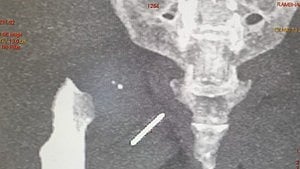

ന്യൂഡല്ഹി: 49 കാരിയുടെ ഇടുപ്പിന്റെ പേശികളില് മൂന്ന് വര്ഷമായി തറഞ്ഞിരുന്ന സൂചി ശസ്ത്രക്രിയയിലൂടെ പുറത്തെടുത്തു. തയ്യലിനിടെയാണ് സൂചി ഇടുപ്പില് തറഞ്ഞ് കയറിയത്. സൂചി തറഞ്ഞ് കയറിയത് അറിയാതിരുന്ന രംഭാ ദേവിക്ക് സ്ഥിരമായി ഇടുപ്പ് വേദനയുണ്ടായിരുന്നു. വേദന വര്ഷം കഴിയുന്തോറും അസഹനീയമാവുകയും തുടര്ന്ന് നടത്തിയ വിശദമായ പരിശോധനകളെത്തുടര്ന്നാണ് സൂചി കണ്ടെത്തിയത്.

തയ്യലിനിടെ ഓര്മിക്കാതെ കട്ടിലില് സൂചി വെച്ച് മറന്നു. മറ്റെന്തോ എടുക്കാന് വേണ്ടി എഴുന്നേറ്റപ്പോള് കാല് വഴുതി കട്ടിലിലേക്ക് വീണു. നല്ല വേദനയുണ്ടായെങ്കിലും സൂചി കുത്തിക്കയറിയതാണെന്ന് മനസിലായില്ല. ഒടിഞ്ഞ ബാക്കി ഭാഗം കട്ടിലില് നിന്ന് കണ്ടെത്തുകയും ചെയ്തു. സൂചിയുടെ ബാക്കി ഭാഗം റൂമിലാണെന്ന് കരുതി നോക്കിയെങ്കിലും കണ്ടെത്താനായില്ല. അതേസമയം, വേദനയുണ്ടായത് വീണതിന്റേതാണെന്നാണ് കരുതിയത്. നാളുകള് കഴിയുമ്പോഴേക്കും വേദന അസഹനീയമായി വര്ധിച്ചു വന്നു. ഇതേത്തുടര്ന്നാണ് ഡോക്ടറെ കാണിക്കാന് തീരുമാനിച്ചത്. എക്സ് റേ എടുത്തപ്പോഴാണ് ഇടുപ്പില് സൂചി കുടുങ്ങിയത് കണ്ടത്.

പിന്നീട് ശസ്ത്രക്രിയ ചെയ്യാന് നോക്കുമ്പോള് പല ഡോക്ടര്മാരും തയ്യാറായില്ല. ശസ്ത്രക്രിയ അതിസങ്കീര്ണമാകുമെന്നതിനാലാണ് ഡോക്ടര്മാര് നിരസിക്കാന് കാരണം. ശസ്ത്രക്രിയ വിജയകരമാണെന്നും രംഭാ ദേവി സുഖമായിരിക്കുന്നുവെന്നും ഡോക്ടര്മാര് പറഞ്ഞു.